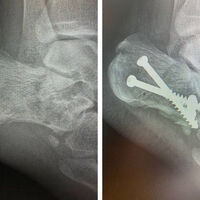

Жительница Волоколамска отправилась к водоему и решила прыгнуть в воду с высокого берега. Она не учла глубину реки в этом месте, поэтому резко столкнулась с дном и сломала обе ноги.

В результате 23-летняя пострадавшая попала в больницу, где медики провели операцию с использованием костной ткани пациентки.

«Собственная ткань приживается быстрее, а установленные в нее импланты служат не меньше, чем смонтированные в натуральной, не оперированной кости», – сообщается в публикации.